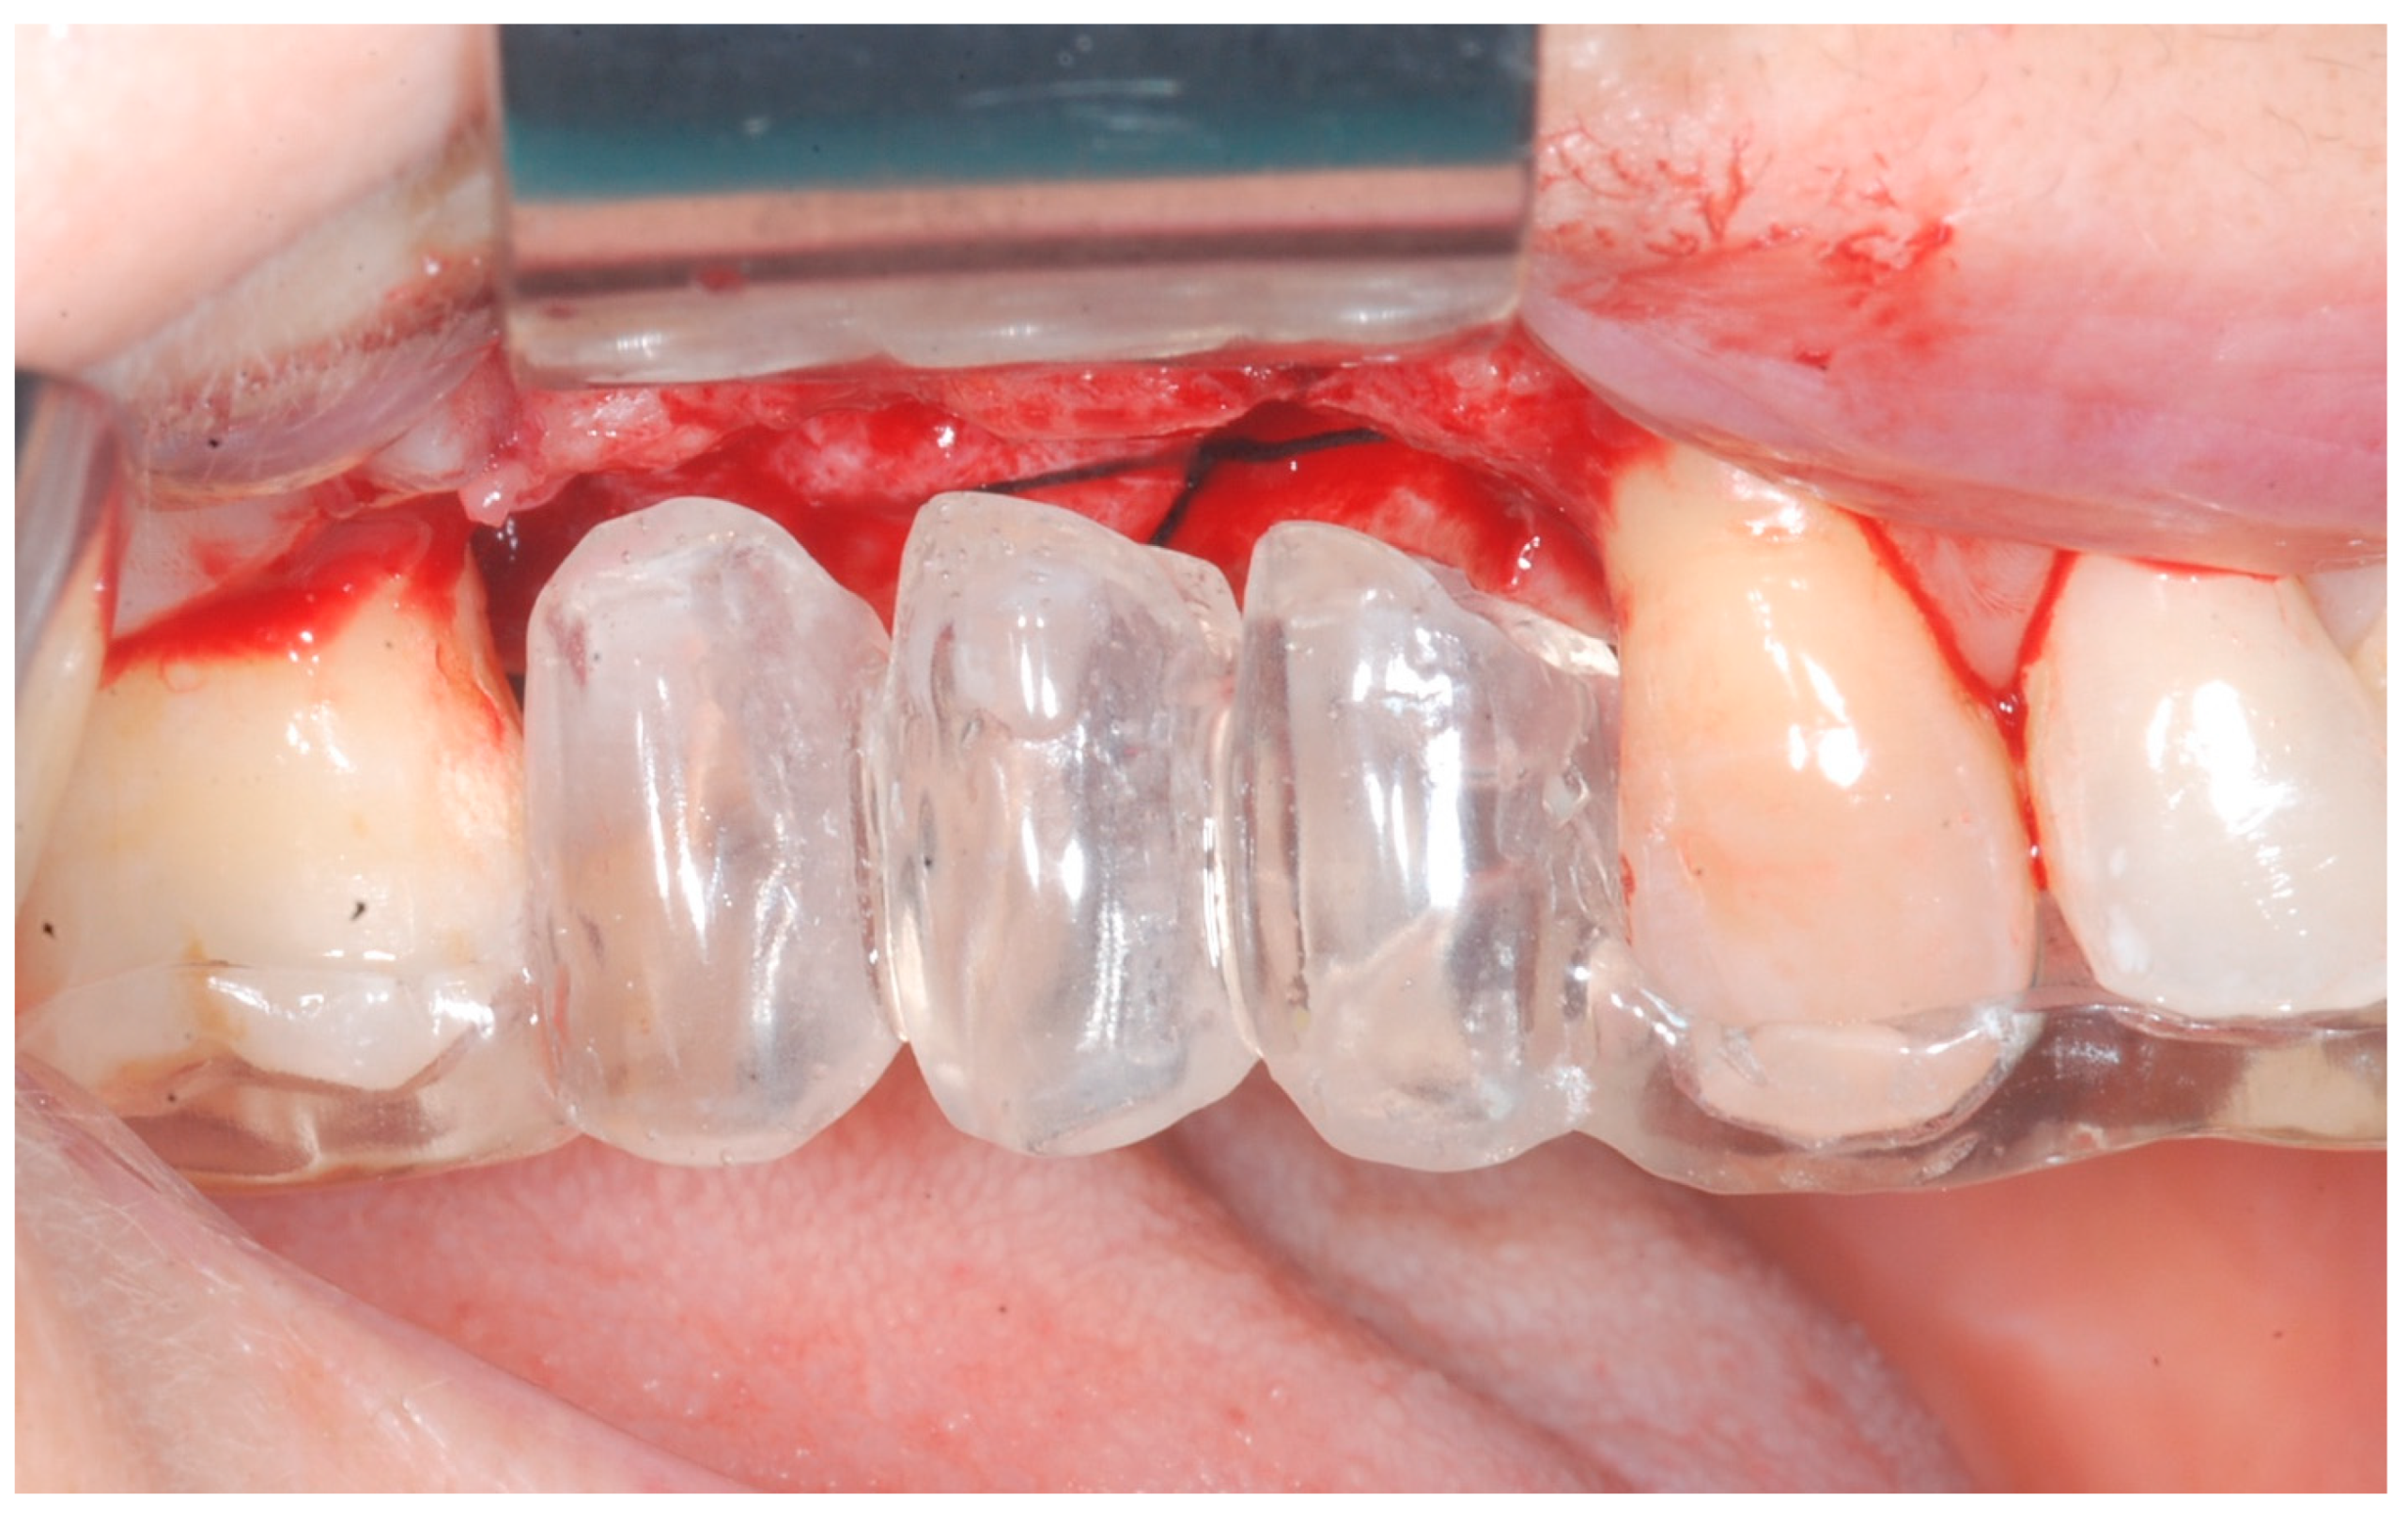

Local anesthesia was obtained with mepivacaine 20 mg/mL with epinephrine 1:100.000 (Optocain, Molteni Dental, Milan, Italy) injections. To raise a mucoperiosteal flap, a crestal incision followed by oblique releasing incisions were made to allow for a wide flap basis as well as sufficient access to the defective ridge area. The flaps were carefully raised using tissue elevators. The bone ridge was examined and any soft tissues remaining on the crest were meticulously removed with a surgical curette (Figure 2).

At this point, implants were placed according to the manufacturer’s instructions in a prosthetically ideal position with the aid of the surgical stent (Figure 3 and Figure 4).

Figure 2. Trapezoidal flap elevation and initial bone thickness.

Figure 3. Surgical stent used for implant positioning.